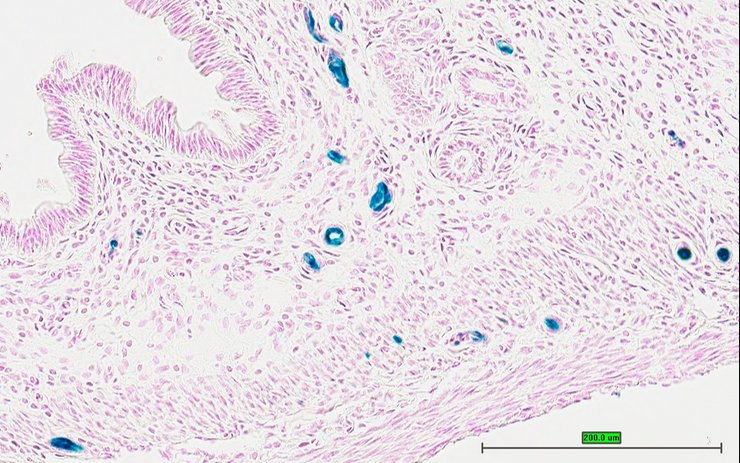

Specimen UC Davis_1879029: postnatal adult; Pmchtm1.1(KOMP)Vlcg/Pmch+ (more )

Structure Level Pattern Image Note

TS28: stomach Present UC Davis_1879029